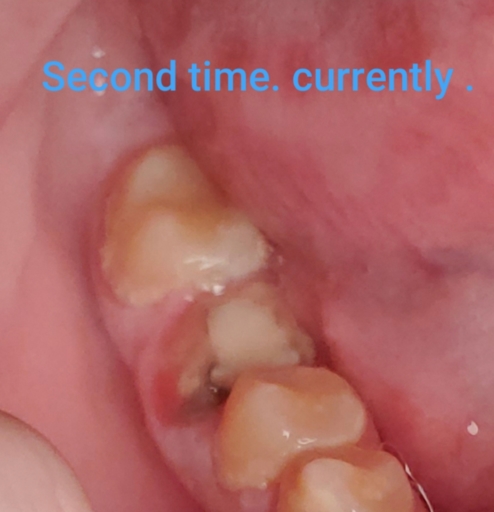

CROWN STRUCTURE BROKEN

My first molar crown came off due to a broken tooth root structure, thus leaving a deep cavity, with very short and small root pieces protruding out of the cavity. Each time I eat, food accumulates in the cavity; thus, I clean well the cavity after each meal, which is causing gum inflammation in the perimeter. Also, I have not had the adjacent piece (premolar) for a long time, which has never bothered me. Pease give me your best advice, considering I would like to cover the cavity permanently in order to avoid food accumulation. Note, I wish to avoid any invasive procedures, such as implant, or the constant discomfort of having a bridge. Thank you

The first step is to have a dental radiograph taken in order to determine if the tooth or teeth are restorable. If they are broken at the gum line as a result of extensive decay, the decay may be on the root surfaces, below the level of the bone. With this type of decay, the long term prognosis is poor and extensive dental treatment would be needed in order to save the teeth. If there isn't root caries present, the teeth may be restorable with full coverage crowns. The longer you wait, the more tooth structure you will loose. This will lead to more necessary dental treatment or unwanted periodontal issues. It is better to go sooner in order to have multiple options for restoring your teeth.